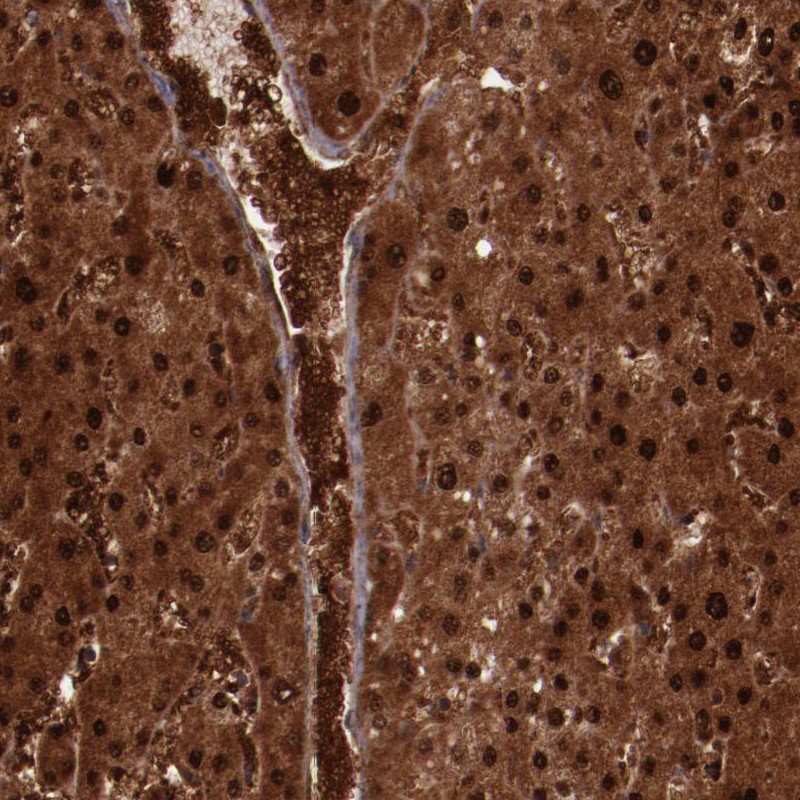

Immunohistochemical staining of human liver shows strong nuclear and cytoplasmic positivity in hepatocytes and extracellular positivity in blood vessels.